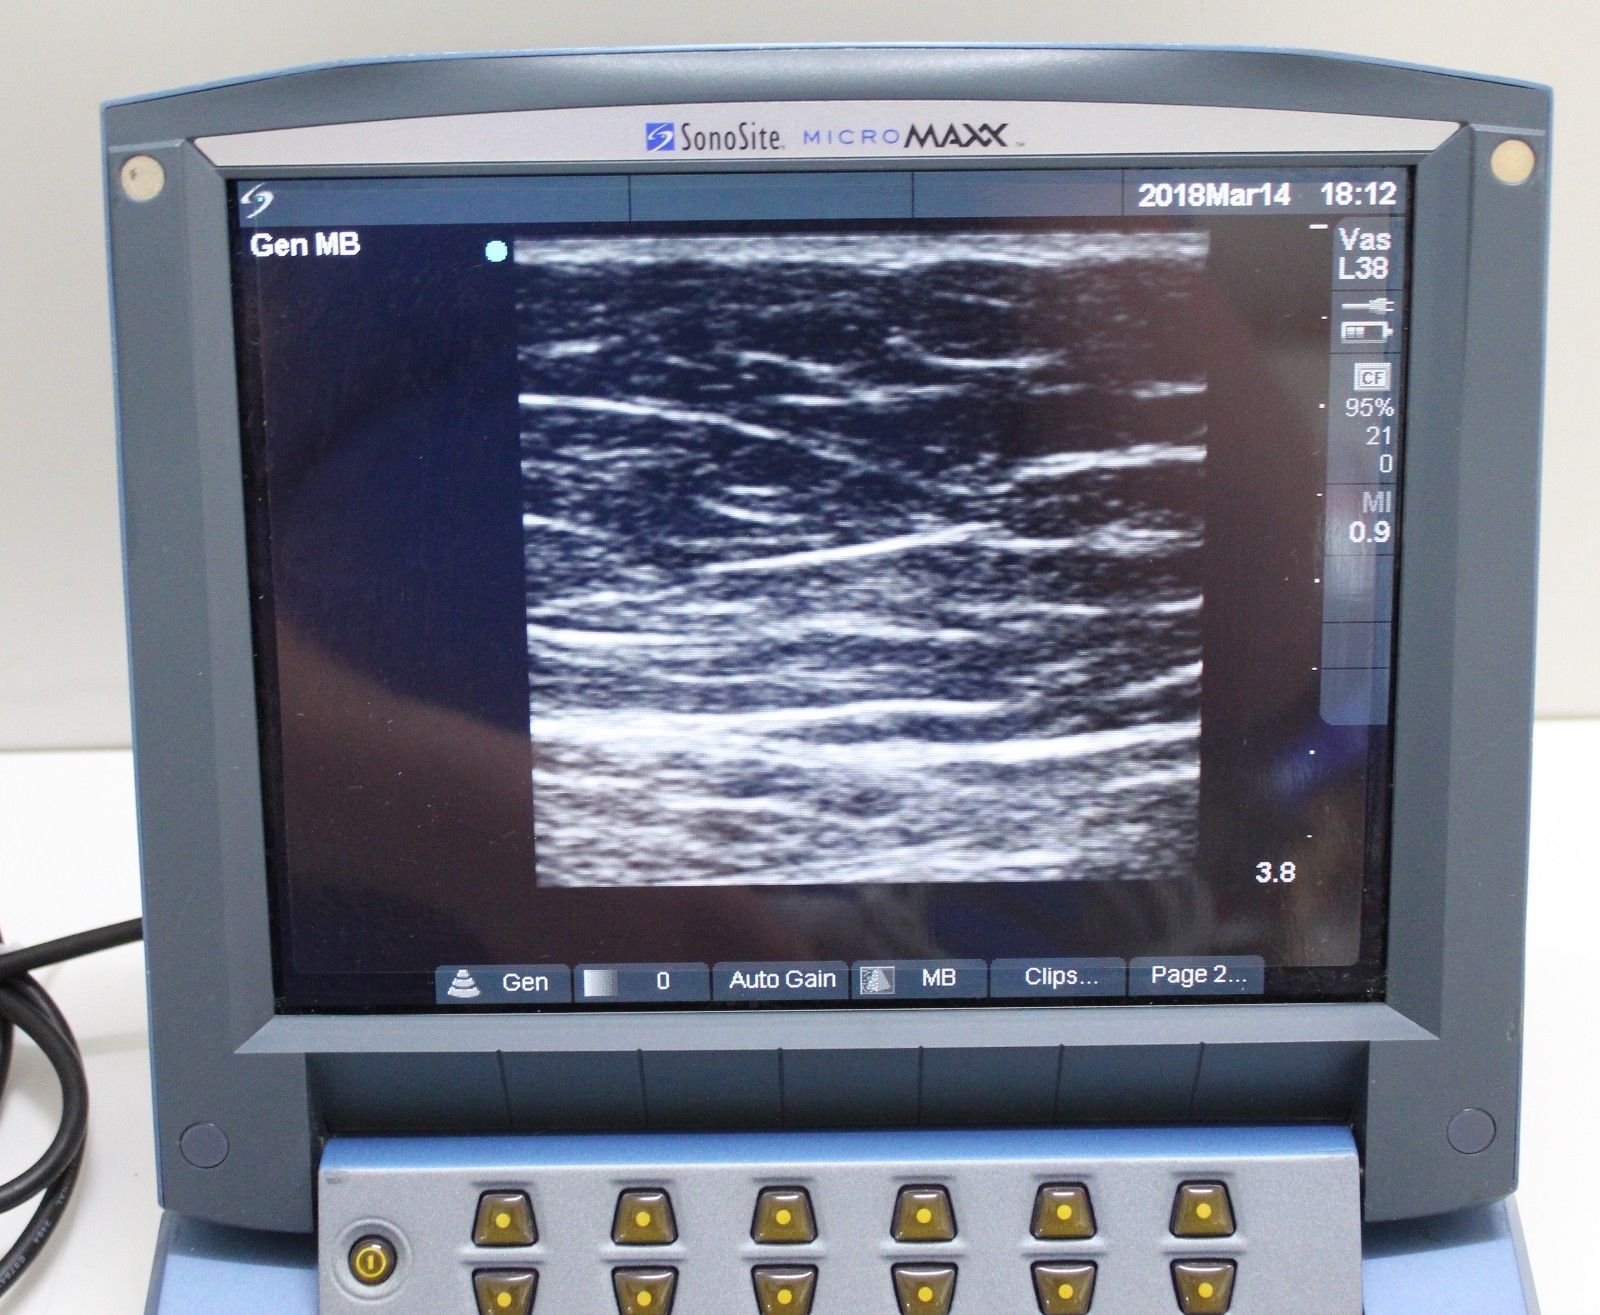

Brand: Sonosite

Model: Micromaxx